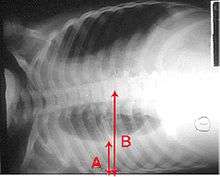

A chest radiograph is frequently used in diagnosis.[19] In people with mild disease, imaging is needed only in those with potential complications, those not having improved with treatment, or those in which the cause is uncertain.[19][48] If a person is sufficiently sick to require hospitalization, a chest radiograph is recommended.[48] Findings do not always match the severity of disease and do not reliably separate between bacterial infection and viral infection.[19]

X-ray presentations of pneumonia may be classified as lobar pneumonia, bronchopneumonia (also known as lobular pneumonia), and interstitial pneumonia.[51] Bacterial, community-acquired pneumonia classically show lung consolidation of one lung segmental lobe, which is known as lobar pneumonia.[29] However, findings may vary, and other patterns are common in other types of pneumonia.[29] Aspiration pneumonia may present with bilateral opacities primarily in the bases of the lungs and on the right side.[29] Radiographs of viral pneumonia may appear normal, appear hyper-inflated, have bilateral patchy areas, or present similar to bacterial pneumonia with lobar consolidation.[29] Radiologic findings may not be present in the early stages of the disease, especially in the presence of dehydration, or may be difficult to be interpreted in the obese or those with a history of lung disease.[20] A CT scan can give additional information in indeterminate cases.[29]